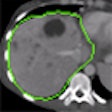

CTA motion model aims to improve cardiac function analysis